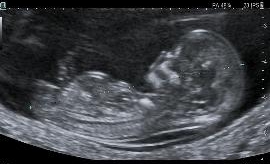

L’échographie de datation

Elle se fait avant 11SA.

Elle permet de localiser, de dater la grossesse et de déterminer le nombre d’embryons evolutifs.

Elle se fait entre 11-13SA+4j.

Elle permet de confirmer la datation par la mesure de la longueur cranio-caudale et de faire un bilan morphologique adapté au terme. Lors de cette échographie, on mesure la clarté de nuque ce qui permettra si le couple le souhaite de faire le dépistage de la trisomie 21.